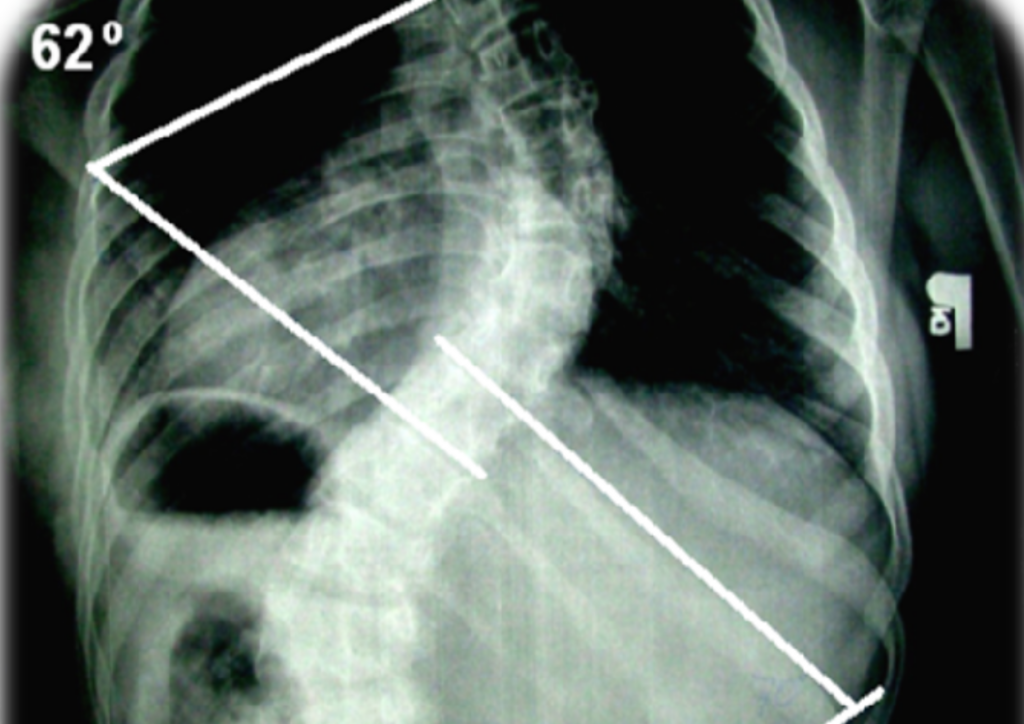

ZOGA MOVEMENT w terapii NIEMOWLĄT cz.I, ZOGA MOVEMENT w terapii NIEMOWLĄT cz.II, Trójwymiarowa terapia stóp, SKOLIOZY – diagnostyka i postepowanie fizjoterapeutyczne, BAC- Body Alignment Concept, ZOGA Therapy w PEDIATRII cz I, ZOGA Therapy w PEDIATRII cz II, Integracja Strukturalna CZASZKI, Zoga therapy wady postawy